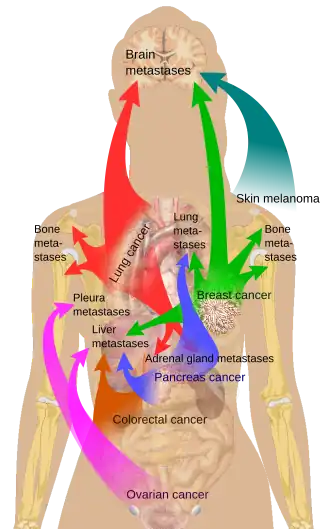

Sources of bone metastases

Bone is the third most common location for metastasis, after the lung and liver.[13] While any type of cancer is capable of forming metastatic tumors within bone, the microenvironment of the marrow tends to favor particular types of cancer, including prostate, breast, and lung cancers.[4] In prostate cancer, bone metastases tend to be the only site of metastasis.[3] The most common sites of bone metastases are the spine, pelvis, ribs, skull, and proximal femur.[10]